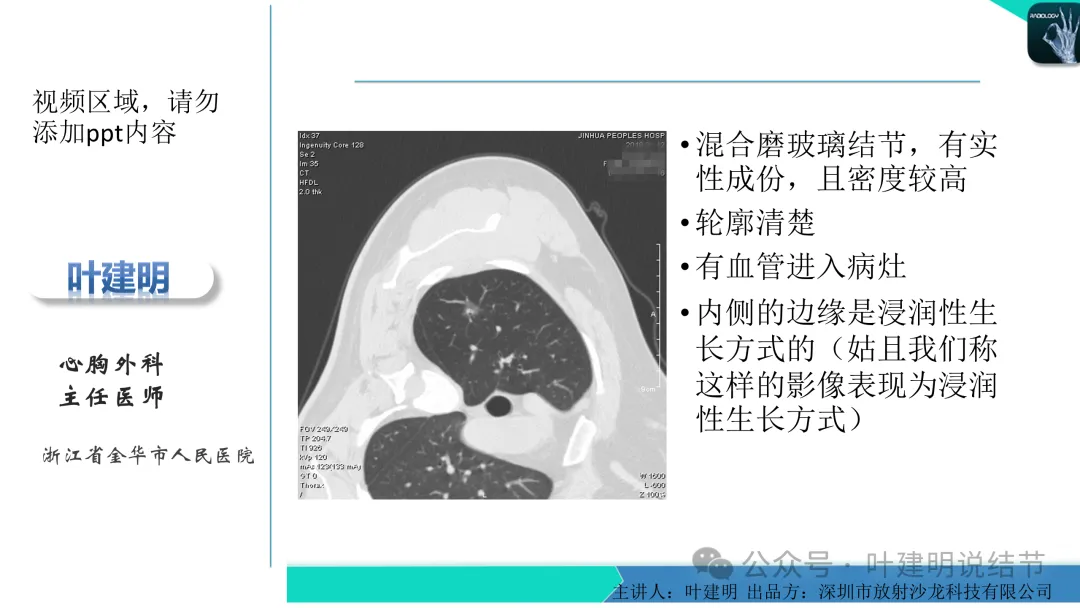

早在2020年时,我受邀在《放射沙龙》做过一个系列的精品课,当时专门总结分析过各类良恶性肺结节与肿块的影像特征,这是当时关于微浸润性腺癌影像特征的分析,今天看来仍基本不太需要改变,大家有兴趣的可以参考: